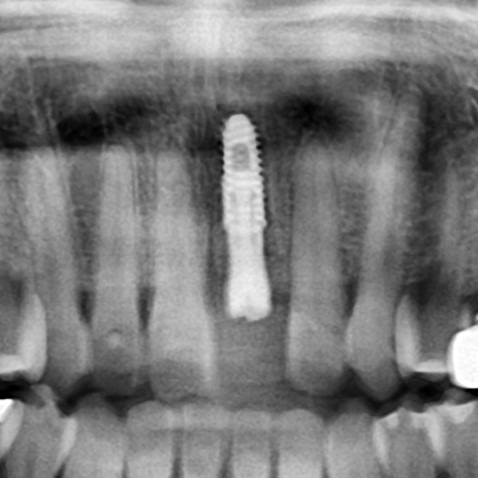

발치와 동시에 임플란트를 식립한 후 방사선사진

임플란트 수술이 잘 이루어지고 난 후에는